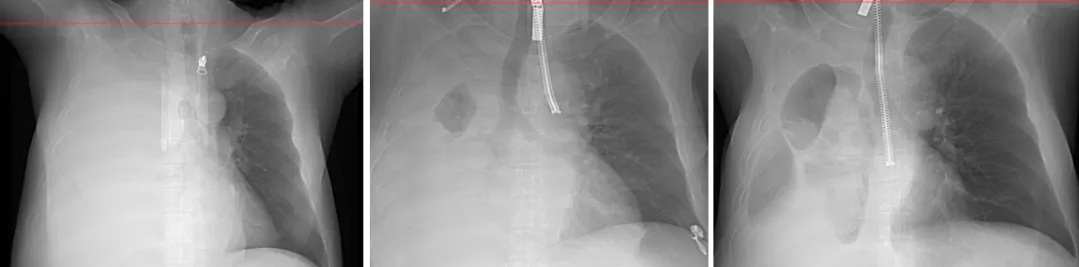

给患者做了肺部CT,发现由于其右侧胸腔积液太多,所以右肺被压的完全张不开了,因此他一动就呼吸困难。这个时候其细菌培养的结果出来了,血和胸水都培养出了肺炎克雷伯菌,这样感染来源,感染病原体都清楚了。

image.png